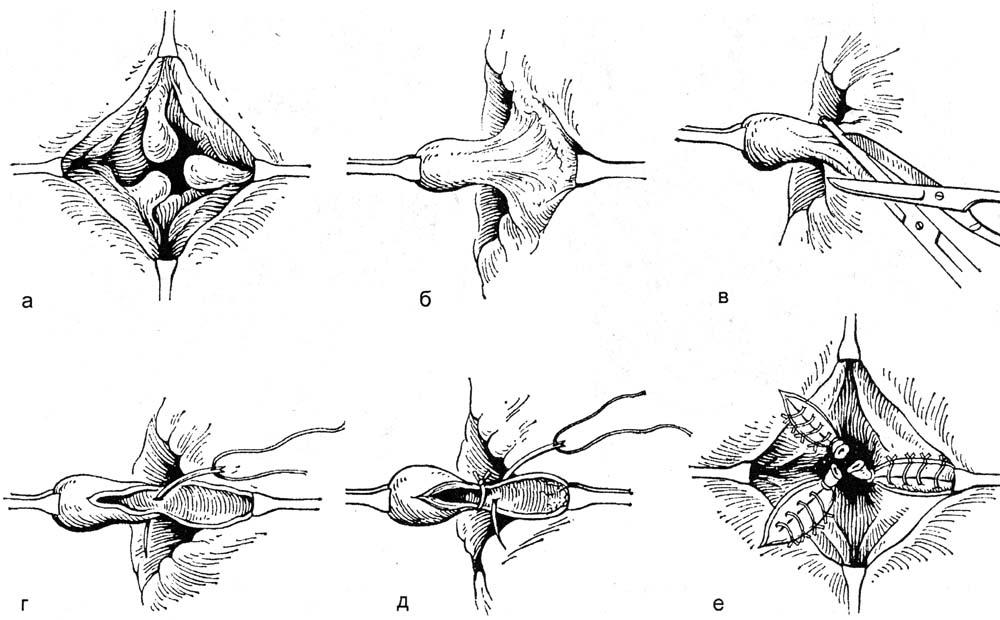

Перинеопластика , также известная как перинеоррафия, включает хирургическую реконструкцию влагалищного входа путем подтягивания мышц промежности и влагалища с целью уменьшения размера влагалищного отверстия.Часто выполняется вместе с задней кольпорафией, это называется кольпоперинеорафией. Обратная перинеопластика включает в себя реконструкцию рубцовой ткани, вызванной склеротическим лишаем, или предшествующая операция предназначена для лечения диспареунии и включает в себя разрез пальпируемых полос и рубца с одновременным созданием лоскута для увеличения интроитального калибра.

Перинеопластика , также известная как перинеоррафия, включает хирургическую реконструкцию влагалищного входа путем подтягивания мышц промежности и влагалища с целью уменьшения размера влагалищного отверстия.Часто выполняется вместе с задней кольпорафией, это называется кольпоперинеорафией. Обратная перинеопластика включает в себя реконструкцию рубцовой ткани, вызванной склеротическим лишаем, или предшествующая операция предназначена для лечения диспареунии и включает в себя разрез пальпируемых полос и рубца с одновременным созданием лоскута для увеличения интроитального калибра.